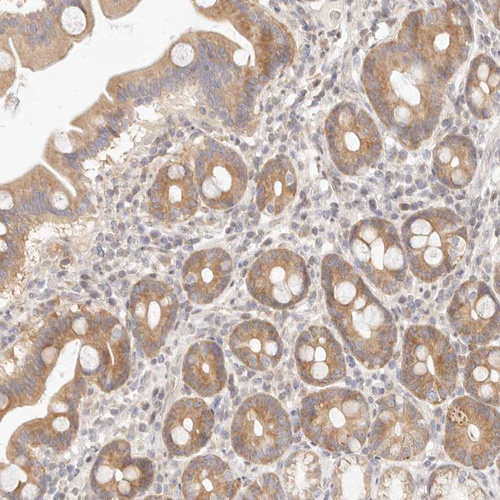

Immunohistochemical staining of human salivary gland shows moderate nuclear and cytoplasmic positivity in glandular cells.